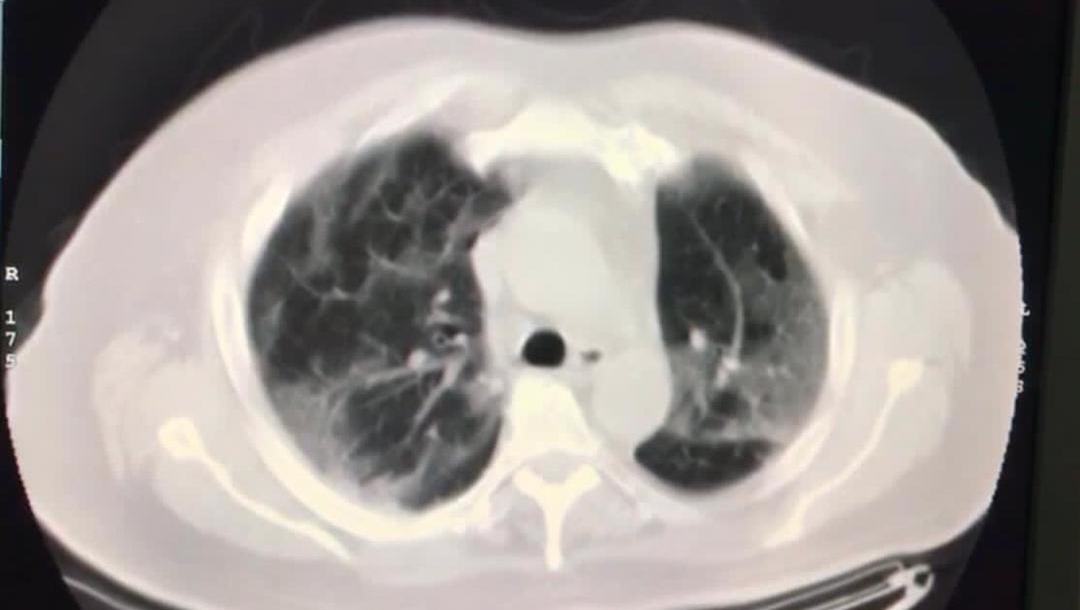

Nuestro querido Arturo, el pasado 27 de junio del presente año desafortunadamente fue diagnosticado con COVID-19. Como se sabe lo que acarrea esta enfermedad, comenzó a presentar disminución de la saturación de oxígeno, por lo que empezó a necesitar el uso de oxígeno suplementario. Inició con bajos requerimientos los cuales fueron aumentando al pasar de los días comprometiendo sus pulmones, posterior a esto, tuvo que ser hospitalizado.